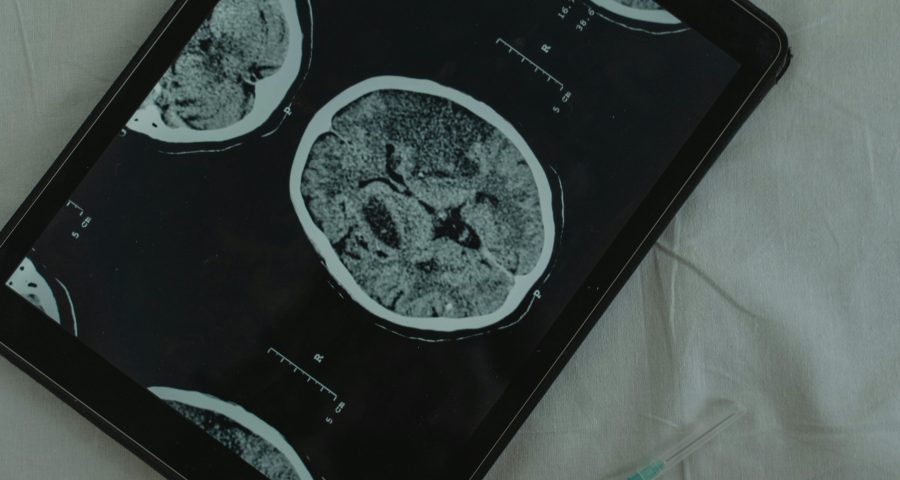

Alzheimer’s sneaks in quietly – but when does it really start? This is Sandra Tsing Loh with the Loh Down on Science. Scientists have long known that Alzheimer’s unfolds slowly. But tracking it? Tricky – until now. Enter Laia Montoliu-Gaya and team at the University of Gothenburg, Sweden. They compared

Continue readingTau Me The Future